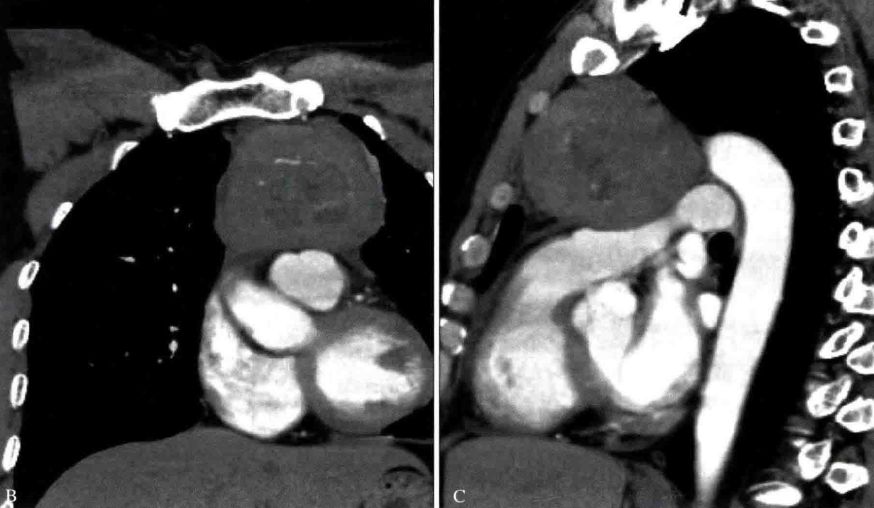

影像表现

胸腺癌影像表现为前纵隔大的肿块,通常边界不清楚,边缘不规则或分叶状,常侵犯并推移邻近结构。常有坏死、出血和(或)囊性变,10% ~ 40%在CT上可见灶状钙化。常侵犯心包、胸膜并出现心包和胸腔积液

胸腺类癌影像表现与常见胸腺上皮肿瘤相仿。当前纵隔肿块伴有库欣综合征时,诊断上应首先考虑为胸腺类癌。MRI上T2WI呈明显呈高信号,可能提示神经内分泌癌的诊断